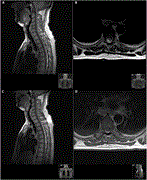

A complex surgery of spinal tuberculosis with a psoas abscess accompanied by fibula autografting: an alternative treatment of Pott’s disease

Marah Mansour and others

Journal of Surgical Case Reports, Volume 2023, Issue 1, January 2023, rjac635, https://doi.org/10.1093/jscr/rjac635